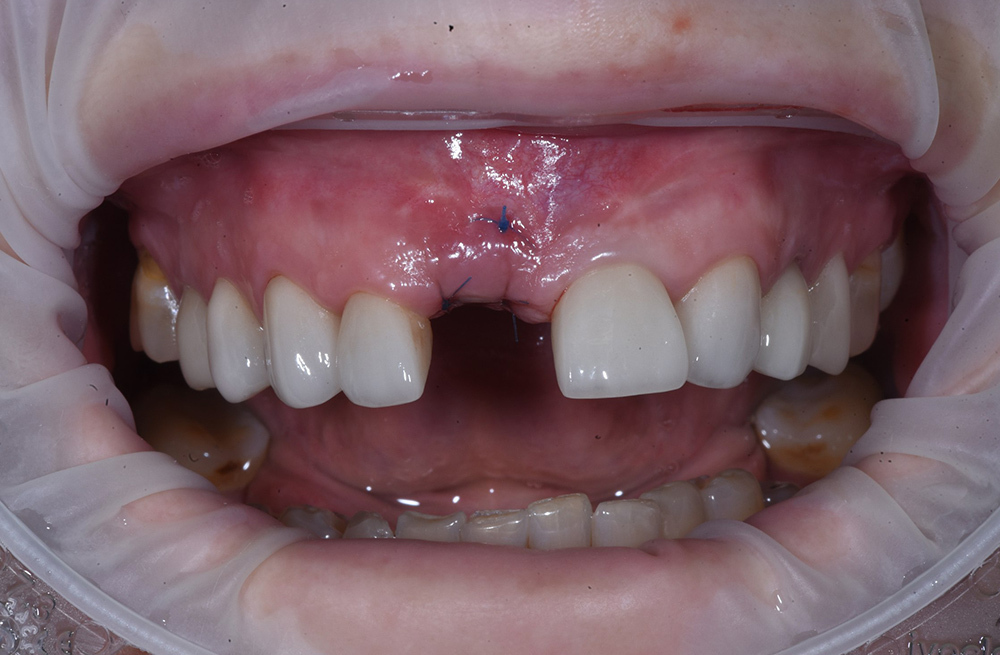

Комплексная реабилитация верхней челюсти после удаления зубов и лечения кисты